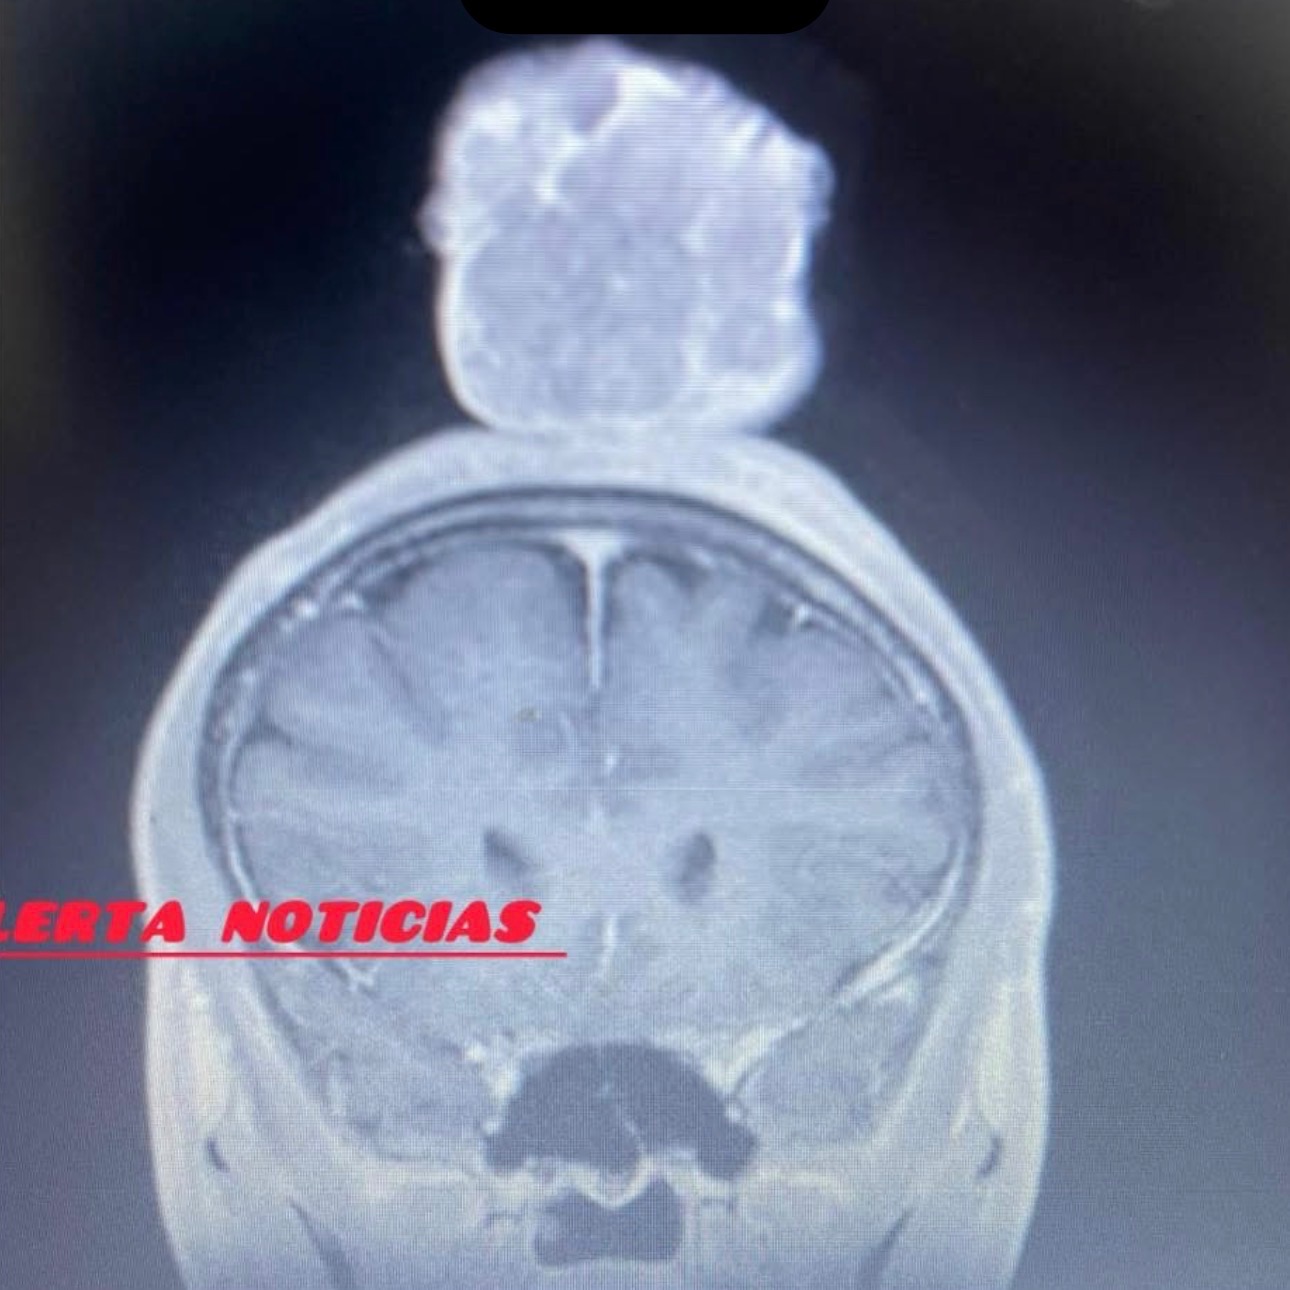

El "grano" que trae en su cabeza los enfermeros comenzaron a manipularlo según para curarlo, llegaban con jeringas a querer succionarlo y lo que hicieron fue que creciera demasiado. Ese "grano" sí fue enviado a patología y el resultado fue que NO es cancerígeno. Sin embargo, del líquido del pulmón no quisieron mandar muestra a patología para confirmar el diagnóstico que ellos aseguraban que era cáncer.

En el IMSS no quisieron retirarle el problema y ahora el "grano", que antes era pequeño, está grandísimo. Algunos especialistas nos dijeron que sí lo operarían pero ya internado, a la mera hora cancelaron por el problema del derrame pleural.

My cousin Angel de Jesús Vega García was diagnosed with testicular cancer two years ago. Last year, he started having problems with pleural effusion in his lung and a lump on his head. He was seeing a general practitioner, but when his cough persisted, the doctor ordered a lung scan, which revealed fluid in his lungs. We were then referred to Clinic 1. That's where the trouble began. According to the doctors, based on his history of testicular cancer, they determined that the fluid in his lung was also cancerous, without performing a biopsy. They inserted a chest tube to drain the fluid, and he was in that position for almost a month, but not much came out. The nurses started manipulating the lump on his head, supposedly to treat it. They would come in with syringes trying to suction it out, but all they did was make it grow much larger. That lump was sent to pathology, and the result was that it is NOT cancerous. However, they refused to send a sample of the lung fluid to pathology to confirm their diagnosis, which they insisted was cancer.